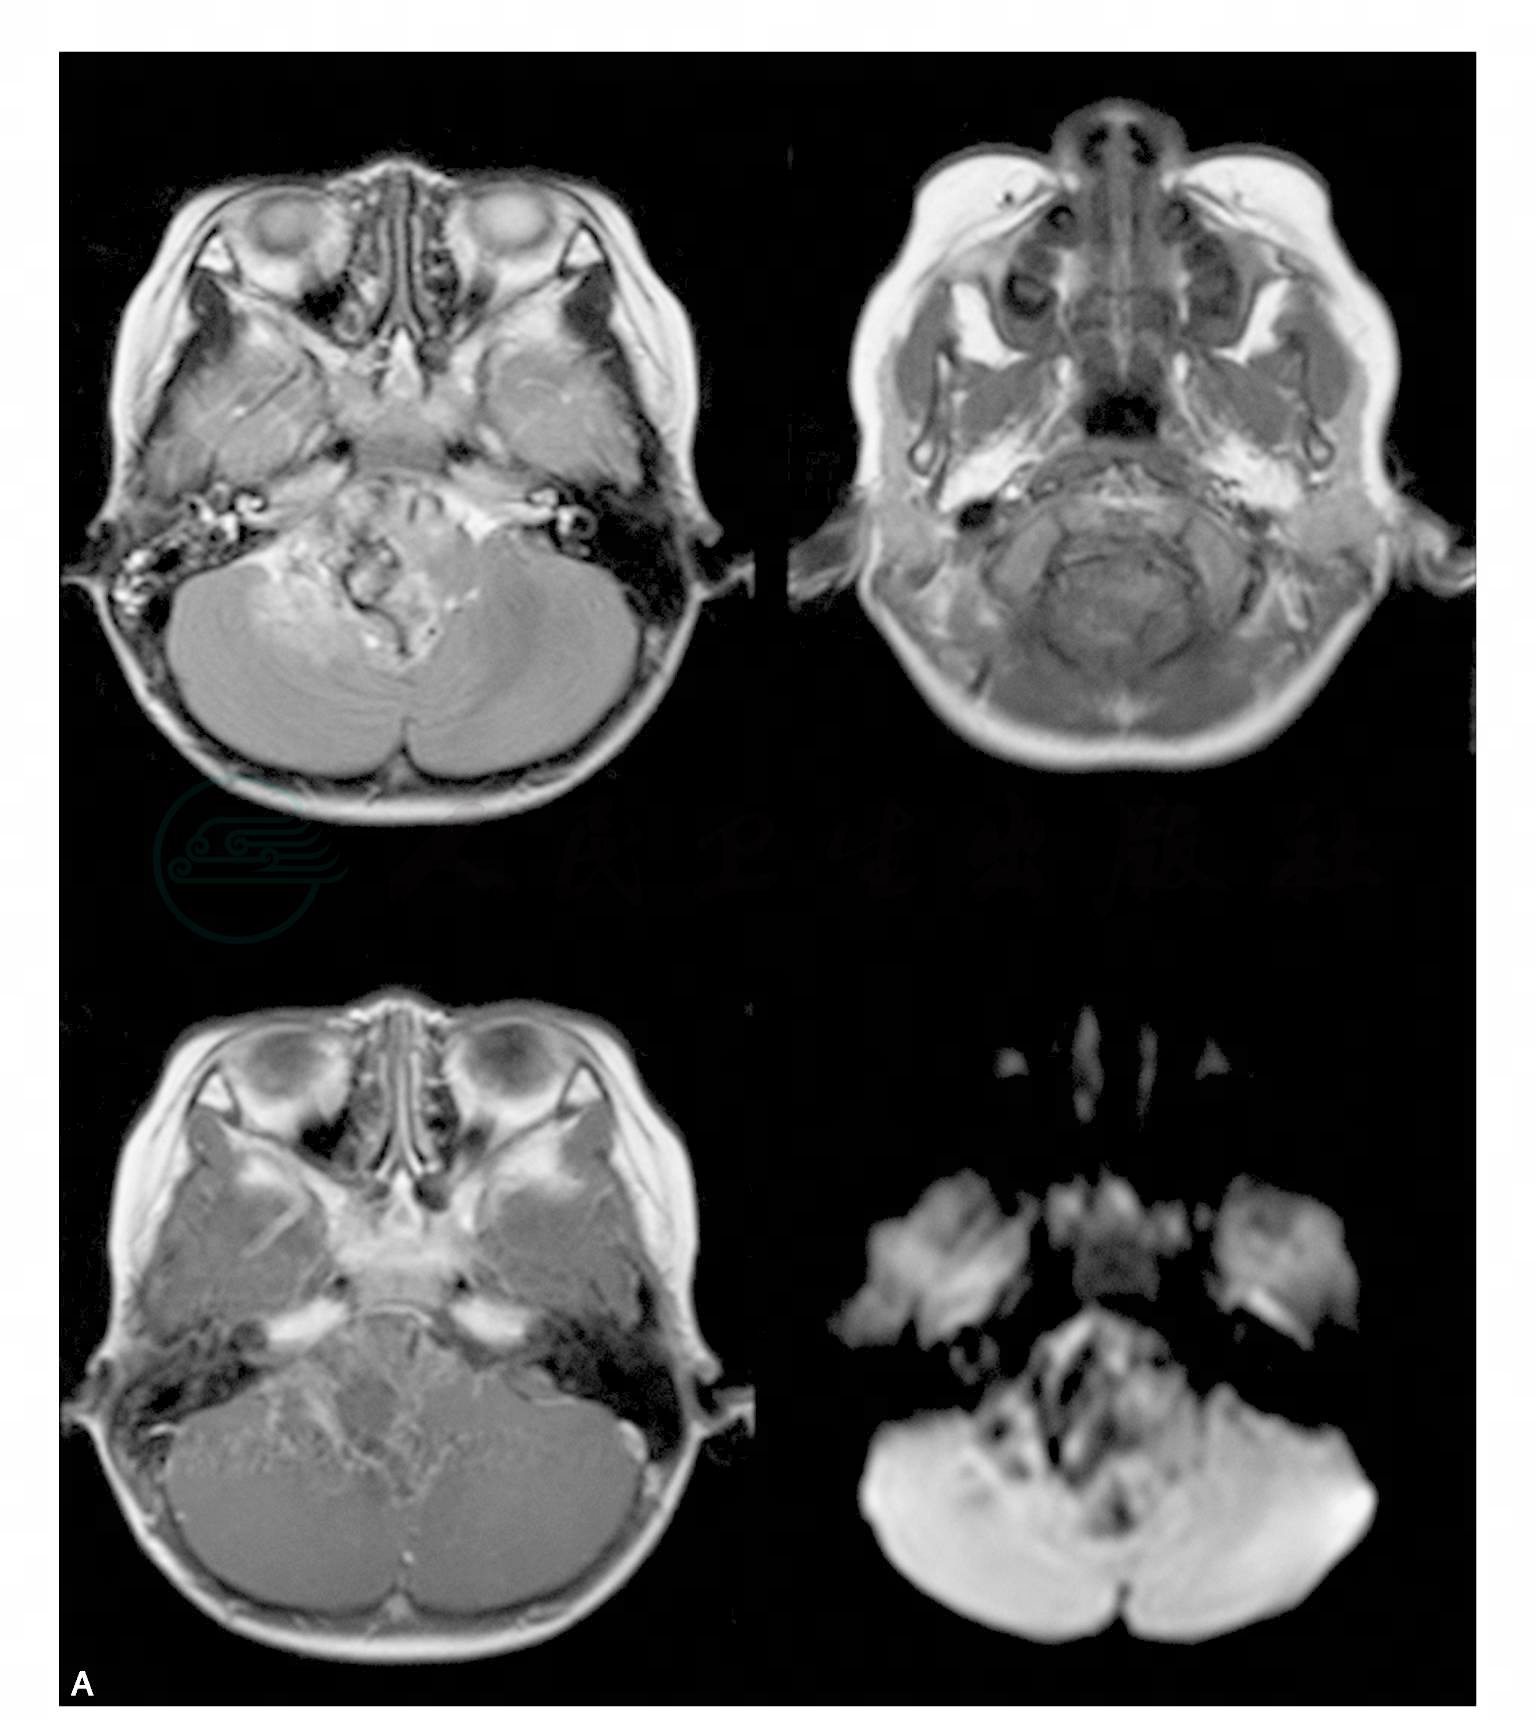

男,5岁,一天前无明显诱因出现头痛,为额部持续胀痛,当时未予特殊治疗。今日仍有头痛症状,进食后呕吐,精神状态差(图1)。

图1 右侧桥小脑区可见类圆形肿块影,以稍长T1稍长T2信号为主,中心可见条状短T1信号影。病灶边界不清,形态不整,第四脑室明显变窄。病变向上生长达脑干,向下生长达延髓。增强扫描病变明显不均匀强化。右侧听神经显示欠佳。幕上脑室普遍增宽,中线结构居中